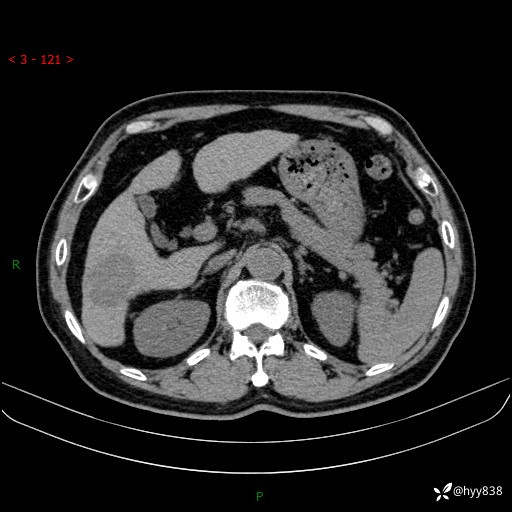

延迟期